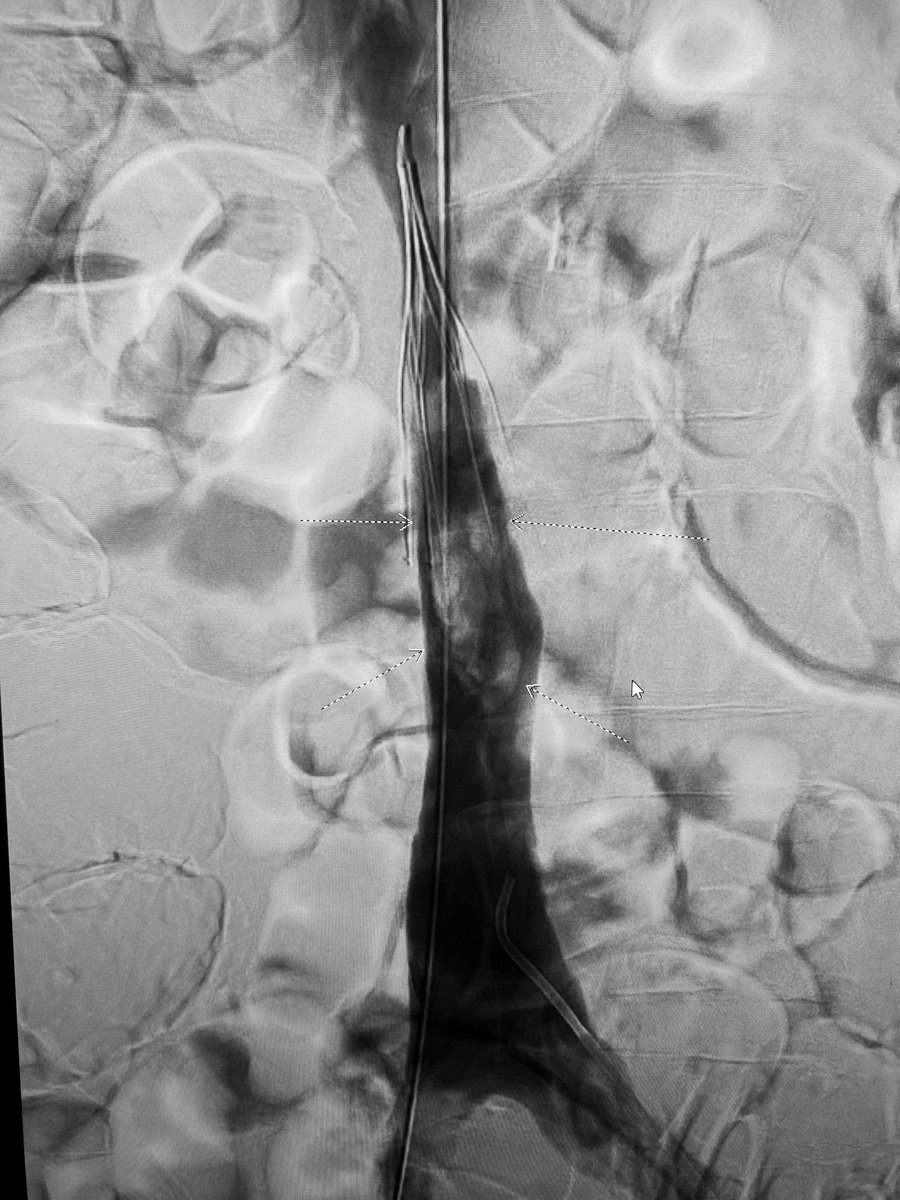

3 month old #IVCfilter with iliocaval occlusion, bilateral leg edema. Crossed both CIV occlusion from below, forceps #Filterout with 18Fr sheath then 18mm wallstent iliocaval reconstruction. #WeCanRecan